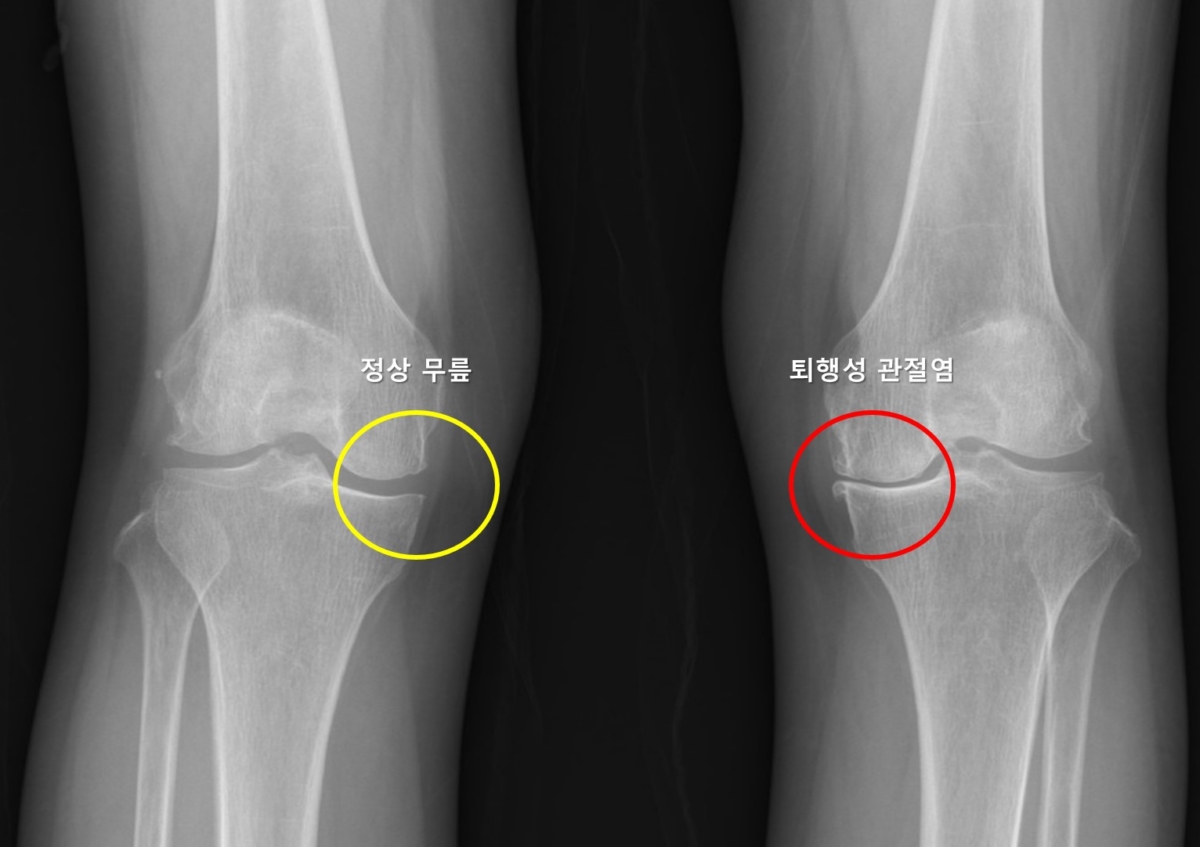

무릎 퇴행성 관절염은 전 세계 인구의 16~30%에서 발생하는 질환이다. 통증과 운동 제한을 유발하며, 삶의 질을 크게 저하시킨다.

한 쪽 무릎에 퇴행성 관절염이 있다면, 시간이 지나 반대편에도 생길 가능성이 건강한 사람에 비해 크다. 모든 환자에게서 반대편에도 관절염이 생기는 건 아니지만 이를 예측하려는 연구는 부족했다.